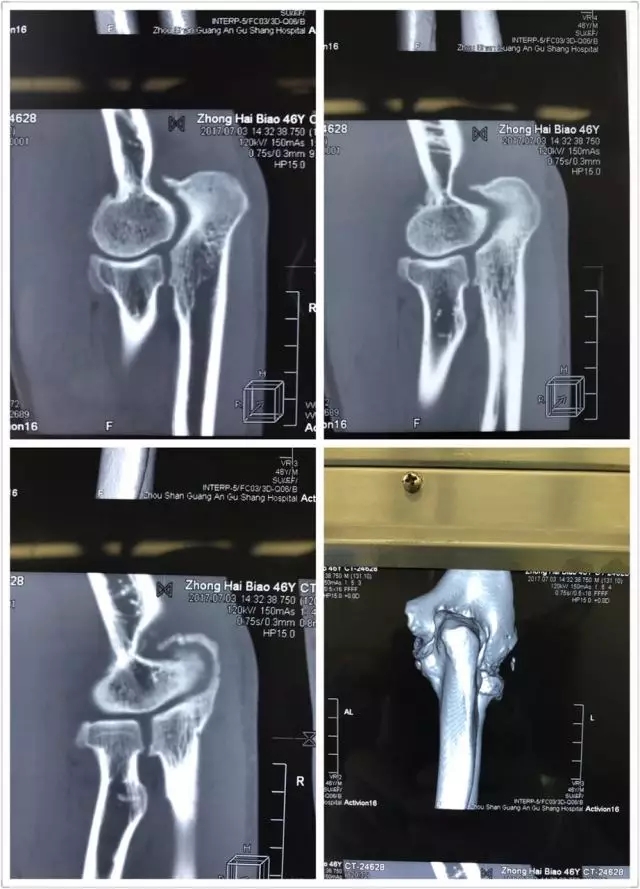

患者鐘某某,男,46歲,漁民,由于一年前的一次手肘部外傷,在受傷后一直隱隱作痛,加上日常生活中勞作過度,所以手臂一直處在“過勞”的狀態(tài)。

近幾個月,持續(xù)的疼痛讓這位輕易不言痛的大男人也忍無可忍,有時候某一個動作所致,會疼得出汗,也有過很多個夜晚無法入眠的疼痛時刻。嘗試過各種止痛藥、膏藥,都無法根除疾病,并逐漸出現(xiàn)肘關(guān)節(jié)不能伸直。

于是他慕名來到舟山廣安醫(yī)院危立軍副院長處就診,診斷為肘關(guān)節(jié)內(nèi)游離體,肘關(guān)節(jié)伸直功能障礙。

舟山廣安醫(yī)院關(guān)節(jié)鏡與運動醫(yī)學(xué)科羅軍主任帶領(lǐng)其王鵬醫(yī)師及團(tuán)隊成員采用國際上先進(jìn)的肘關(guān)節(jié)鏡技術(shù),為這位患者施行肘關(guān)節(jié)鏡下游離體取出,骨贅清除,尺骨鷹嘴窩成形術(shù),術(shù)后患者癥狀明顯好轉(zhuǎn),折磨了一年多的疼痛消失了,臉上重新露出了笑容。